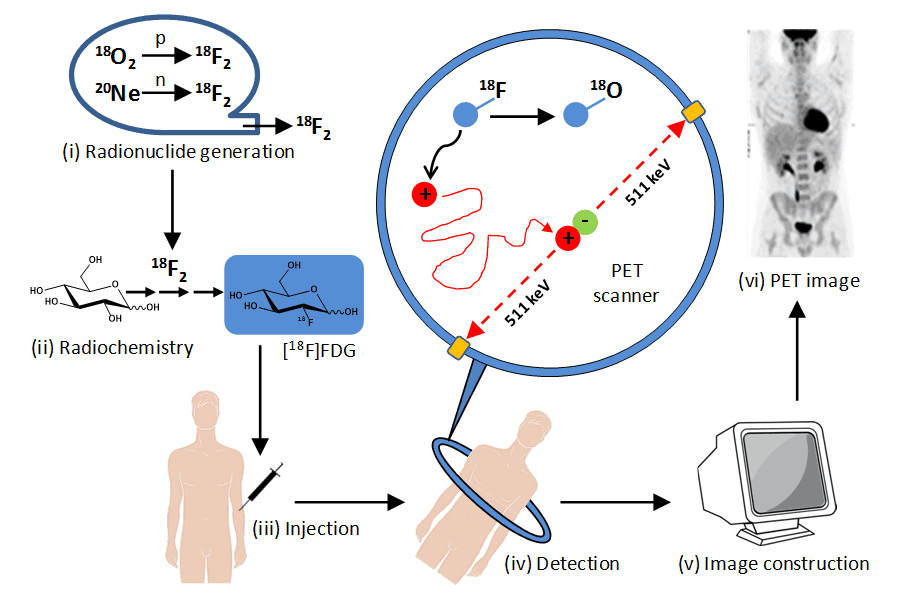

Medical Imaging Modalities Medical Radiation Open Medscience

https://openmedscience.com/wp-content/uploads/2015/02/Figure-2.-PET-Imaging.png